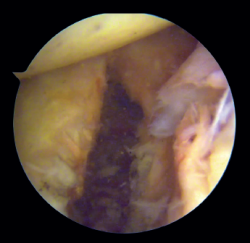

Arthroscope is introduced through the anterosuperior portal, and the glenoid guide is introduced through the posterior portal, and passed paralel to the glenoid surface until the hook is located at the centre of the bone defect. The guide is secured with two cannulas inserted through two small accessory incisions, until connecting with the posterior cortical layer. Both cortical layers are drilled through them using a 2.8 mm drill fitted with a sheath so that on withdrawing the drill the sheath is positioned at drilling level. This step is made twice to introduce two sheaths: one above and the other below the glenoid guide hook and spaced 10 mm apart. Through these sheaths we advance two monofilament loops that are retrieved sequentially through the anterior portal for subsequent passing of the graft. At this point we can remove both sheaths and the glenoid guide, taking care to prevent the guide hook from coming into contact with the glenoid surface in order to avoid damaging to the cartilage.

Figure 3. View from the anterosuperior portal (left shoulder). Monofilaments inserted through the sheaths from posterior to anterior for subsequent passing of the threads that will introduce the graft.